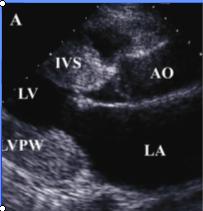

3.超聲心動圖確診RCM的重要方法,約82%的患者表現為心室腔狹小、心尖閉塞、心內膜回聲增強、房室瓣關閉不全、心房擴大和附壁血栓,二尖瓣葉呈多層反射、後葉常無活動。心室舒張早期內徑可增大,經二尖瓣血流加速導致E峰高尖,但E峰減速時間縮短(shorteneddecelerationtime),常≤150ms,都卜勒血流圖可見舒張期快速充盈突然中止;舒張中、晚期心室內徑無繼續擴大,A峰減低,E/A比值增大,具體標準為:E峰≥1.0m/s,A峰≤0.5m/s,E/A比值≥2.0,等容舒張時間縮短≤70ms。